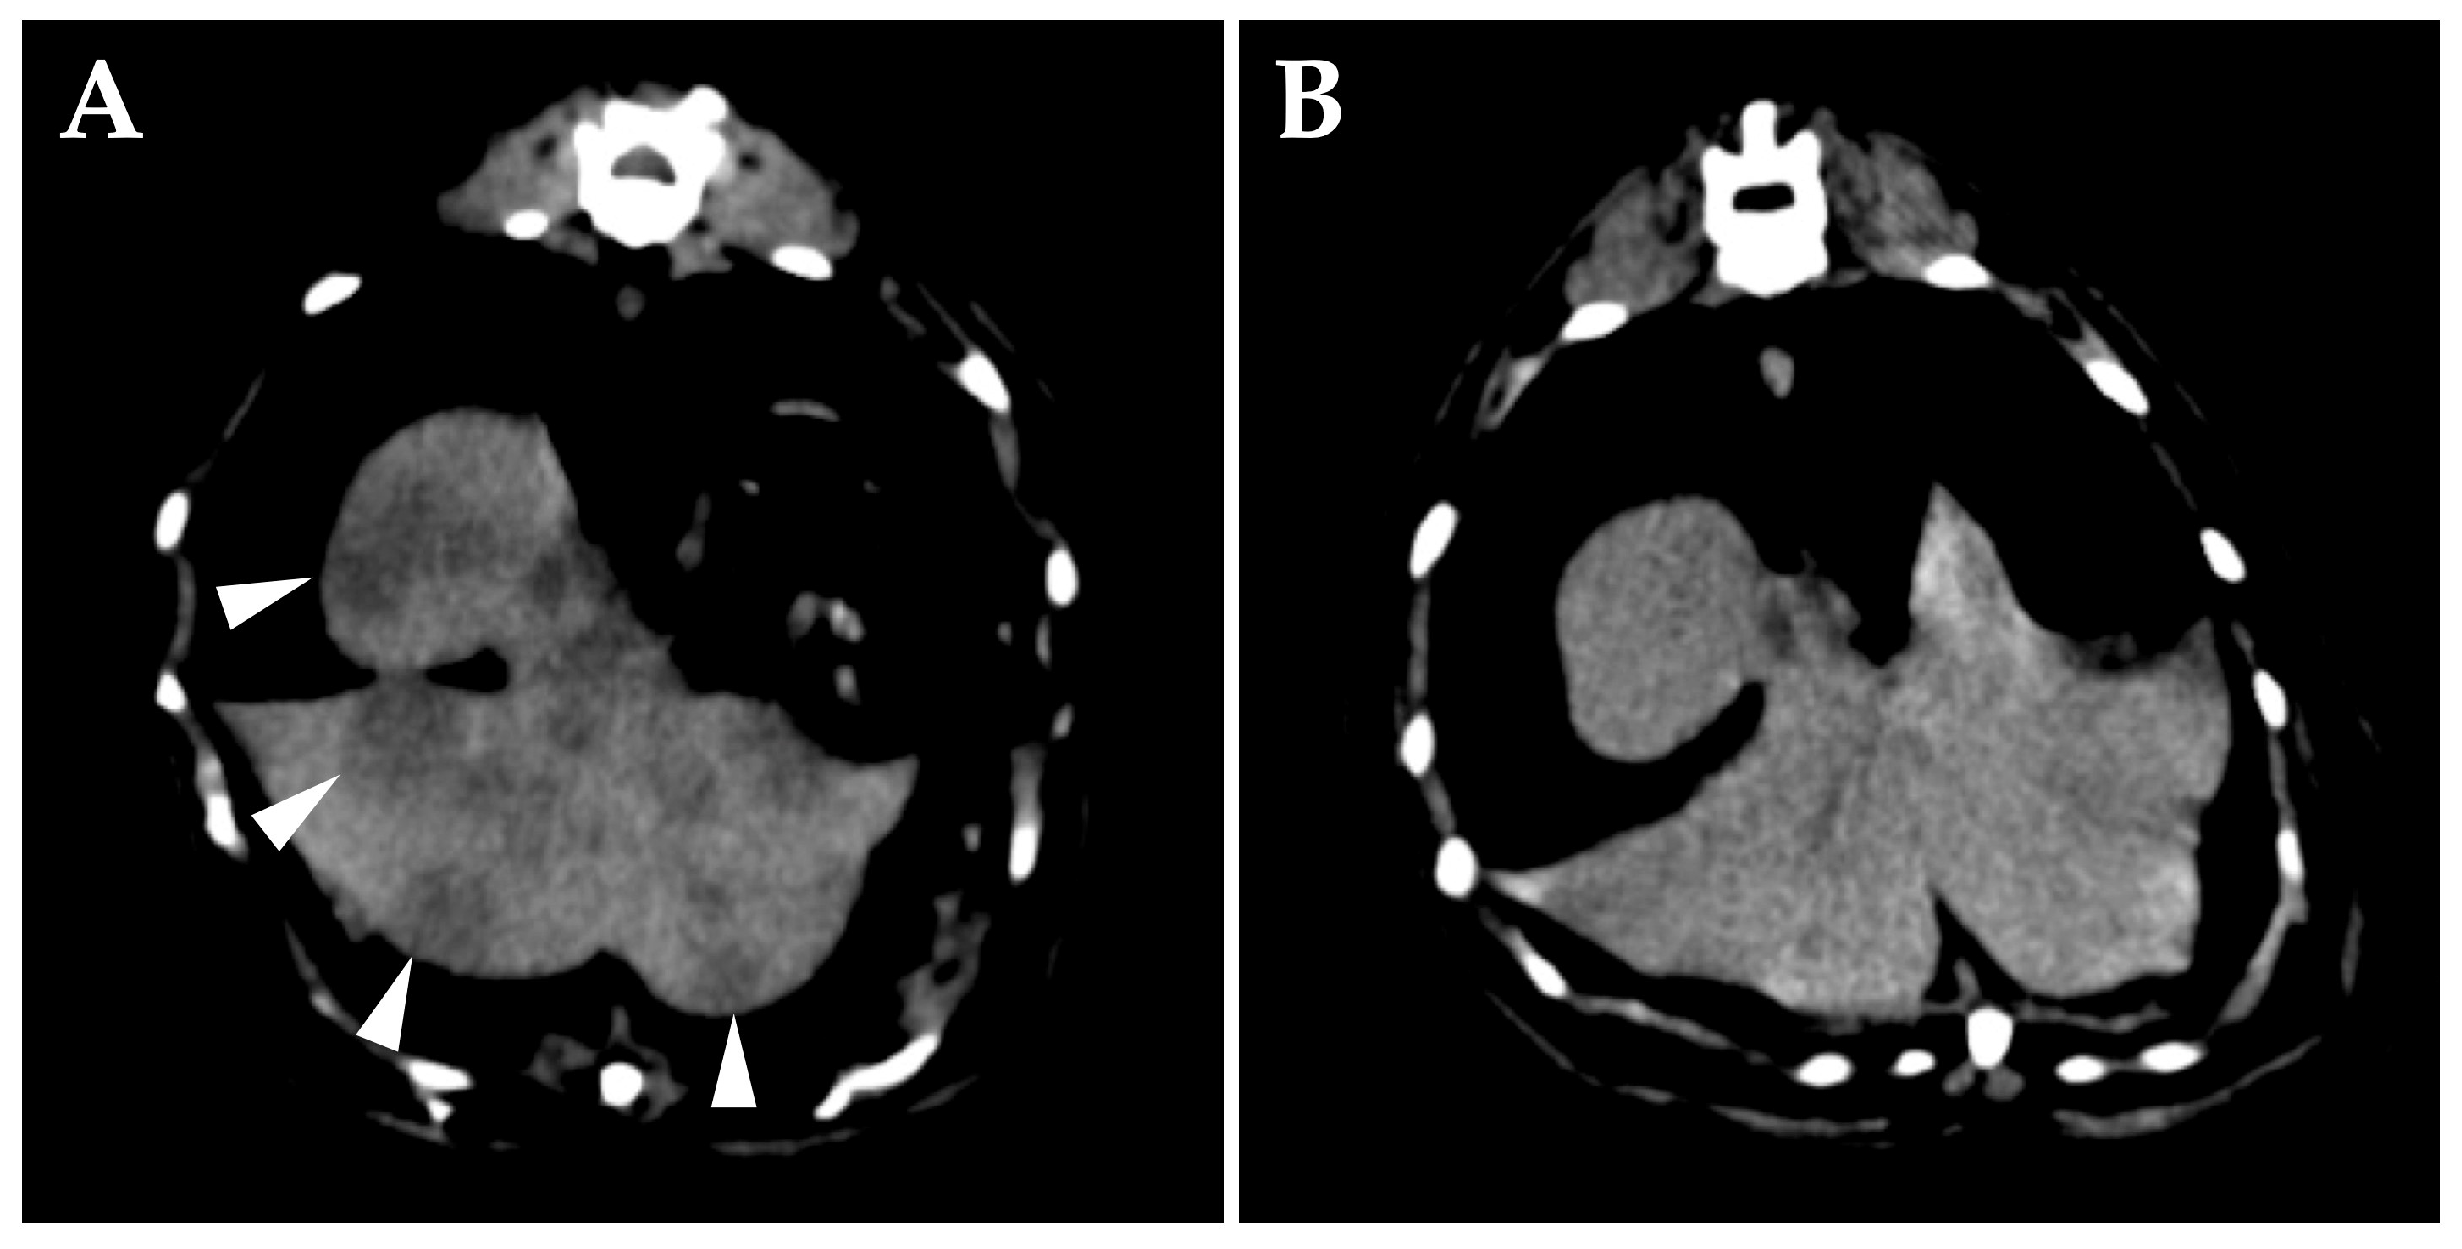

At the time of initial examination, she weighed 3.60 kg and there were no obvious abnormalities in the posture or gait. There was minimal earwax and no enlarged cervical lymph nodes. A cranial neurologic examination was performed, which revealed a disturbance of the right facial nerve and abnormalities of the hypoglossal nerve (narrowing of the right eyelid fissure, loss of right menace reaction, loss of right eyelid reflex, decreased right corneal reflex, decreased right maxillary and mandible perception, and folded tongue). There was no history of seizures. Complete blood count, blood biochemistry, coagulation test, and urinalysis showed no obvious abnormalities. Feline immunodeficiency virus antibody test and feline leukemia virus antigen test were negative (SNAP FIV/FeLV Combo Test; IDEXX Laboratories, Inc., Westbrook, Me, USA). A computed tomography (CT) scan of the head (without anesthesia/without contrast media) was performed to confirm the status of the middle ear, which revealed occupying lesions in the bilateral tympanic bulla (Figure 1). There were no obvious bony changes and no obvious abnormalities other than the middle ear, including the nasal cavity. The lesions within the tympanic bulla seemed like an effusion or soft tissue, and infection and neoplastic disease were the differential diagnoses.

Figure 1. Transverse computed tomography images of the head at the level of the middle ear of the cat at first presentation (without anesthesia/without contrast), in soft tissue window (A) and bony window (B). The ventromedial compartment of the left tympanic bulla and the ventromedial and dorsolateral compartment of the right tympanic bulla are occupied by fluid/soft tissue attenuating materials. There is no bony abnormality.